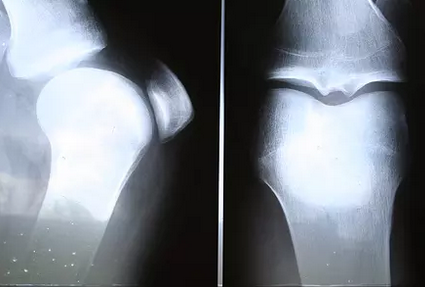

膝关节是人体最大的关节,由于活动范围较大,所以损伤的机会也是比较多的关节。平时的上下楼梯、坐起立行等的情况,均是可以损伤到膝关节的情况的,所以膝关节出现病变的情况多发生在中老年人时期。当出现膝关节疾病的情况,则将会影响到人体的行动能力,而且还会让人出现疼痛不适的症状,让人们的生活质量下降。那么膝关节骨关节炎如何治疗呢?这就是今天小编给大家介绍的内容。

膝关节骨关节炎主要的治疗方法是减少关节的负重和过度的大幅度活动,以延缓病情变化的进度。如使用拐杖行走,使用夹板支架,控制体重等;另外还需要注意避免长时间下蹲或是站立,注意行走的姿势等等。